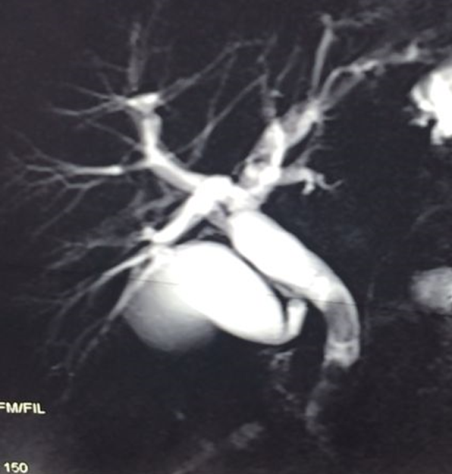

Axacaq zədələnmələri yerinə görə 3 böyük qrupa bölünür: magistral, şaxə və izolə axarların zədələnmələri (Şəkil 1).

Şəkil 1. Axacaq zədələnmələrinin yerinə görə növləri

- Magistral axacaqlara pay, haça, ümumi qaraciyər axacağı və xoledox aid edilir. Bu axarların tam, hissəvi kəsilməsi və ya bağlanması öd sızması və/və ya mexaniki sarılıqla biruzə verir, kontrastlı xolangioqrafiya ilə təyin olunurlar, adətən sızıntı və striktura törədirlər, müalicəsi üçün bərpa və ya rekonstruksiya lazım gəlir.

- Şaxə axacaqlara magistral axacaq sistemi ilə əlaqəli olan kiçik axacaqlar - kisə axacağı, Luşka axacaqları, seqment axarları aid edilir. Bu axarların zədələnmələrini açıq qalmaları, kəsilmələri və ya klipin sürüşməsi təşkil edir. Bu zədələnmələr adətən öd sızması ilə biruzə verirlər, kontrast xolangioqrafiyada diaqnozunu dəqiqləşdirmək mümkün olur, öd fistulu spontan və ya öd yollarının dekompressiyası ilə aradan qalxa bilir.

- İzolə axacaqlara magistral axacaq sistemi ilə əlaqəsi olmayan axacaqlar - əlavə seqment və subseqmentar axacaqlar aid edilir. Bu axacaqların zədələnmələrini bağlanmaları və ya açıq qalmaları təşkil edir. İzolə axacaq zədələnmələri öd sızması (açıq qalarsa) və ya lokal mexaniki sarılıqla (bağlanarsa) ortaya çıxırlar, kontrast xolangioqrafiyada görünmürlər, öd fistulu spontan bağlanmır və ya uzun müddətə bağlanır, lokal abses və atrofiya törədə bilir.

- Zədələnmələrin olub-olmamasını, yеrini və xaraktеrini dəqiqləşdirmək üçün xolangioqrafiya еdilir. MRT ilk seçimdir, lakin dəqiqləşdirmə üçün adətən kontrastlı xolangioqrafiya edilir: əməliyyat vaxtı əməliyyatdaxili xolangioqrafiya, əməliyyatdan sonra isə endoskopik və ya perkutan xolangioqrafiya.

- Öd yollarına yeridilən kontrastın kənara çıxması və ya “blok” (bağlanma) zədələnməni təsdiqləyən əlamətləridir.

- Xolangioqrafiyada biliar ekstravazasiya və ya blok